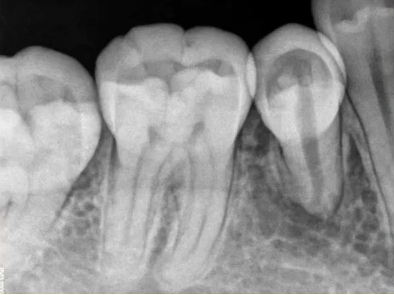

二次拍根尖片确认可看到根尖低密度炎症,临床检查与影像学检查相符,是根尖周炎。

曲面断层片怎么看口腔精读 | 一次性教你看懂曲面断层片!_https://www.jmylbn.com_新闻资讯_第21张

临床检查45叩诊(+),牙颌面见畸形中央尖。加拍根尖片可看到,右下5根方有低密度影,并且右下5的牙根较短小,和曲面断层片上显示的大小不同,所以右下5是舌向倾斜的牙齿。

曲面断层片怎么看口腔精读 | 一次性教你看懂曲面断层片!_https://www.jmylbn.com_新闻资讯_第25张